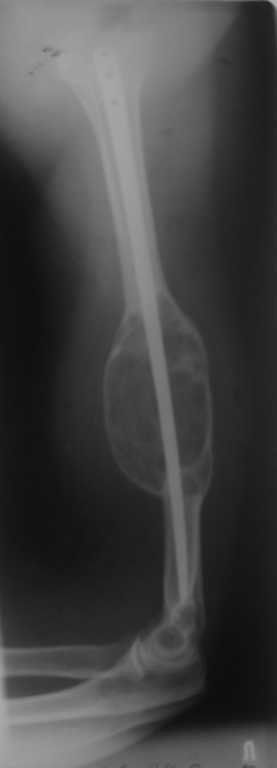

[Ortho] Хондросаркома плечевой кости?

Уважаемые коллеги! 3 года назад оперирована пациентка по поводу патологического перелома

плеча на фоне костной кисты. Выполнен ЗИО плоским титановым стержнем. Спустя 1,5 года на фоне

сросшегося перелома выявлен рост опухоли, подозрение на малигнизацию. Консультирована

онкологами, те пациентку своей не признали, биопсия не проводилась. Биопсия выполнена в

июне 2009, по заключению одного учреждения - костная киста, по другому - хондросаркома.

Обследована, отдаленных метастазов нет.

Вопросы: Диагноз? Варианты лечения? Может, резекция в пределах

здоровой кости, каркасная металлопластика плюс гвоздь? Спасибо.